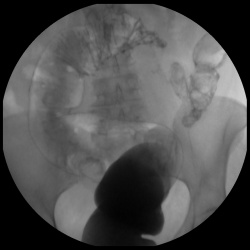

Мужчина, возраст 60 лет. При шёл на обследование брюшной полости. Был направлен дерматологом, так как имеет кожные высыпания, диагноз не ясен. В прошлом, часто находился в африканских странах,...